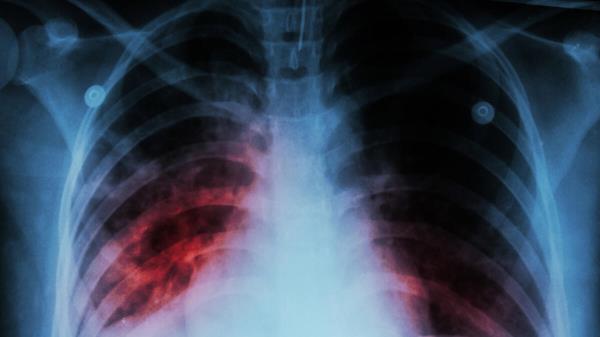

“当鼻喷DNA融合疫苗与一线结核药物联合使用时,受感染小鼠的病原菌清除速度显著加快,肺部炎症减轻,治疗结束后更有效防止了病情复发。”研究负责人斯泰利亚尼·卡拉尼卡强调。她身兼约翰斯·霍普金斯大学结核病研究中心核心成员与医学院助理教授双职,该结论已通过校方官网发布。

她进一步阐释,采用鼻喷给药能将免疫反应精准聚焦于鼻窦与肺部黏膜——这正是感染发生的起始阵地。

据世界卫生组织界定,结核病是由细菌引发的传染性疾病,通常通过咳嗽传播并侵袭肺部。2024年全球新增感染超1000万例中,约120万人因此丧生;全球约四分之一人口携带结核杆菌而无症状,其中5%至10%会发展为活动性结核病。婴幼儿一旦感染,患病风险尤为突出。

典型症状包括持续咳嗽(有时带血)、胸痛、虚弱乏力、体重下降、发热及夜间盗汗。该病通常需抗生素治疗,若放任不管可能致命。